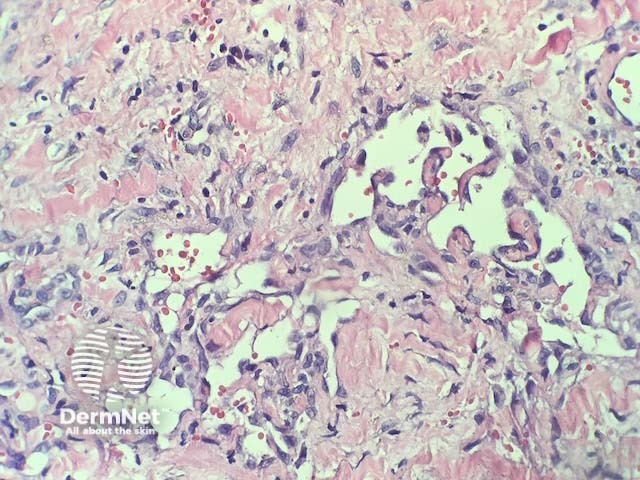

In verrucous haemangioma, the histopathology shows irregular papillomatosis, acanthosis and hyperkeratosis of the epidermis. The dermis shows multiple, thin-walled, dilated blood-filled spaces. Intravascular thrombosis with recanalisation and haemorrhage can be seen (figures 1–5).

Figure 4